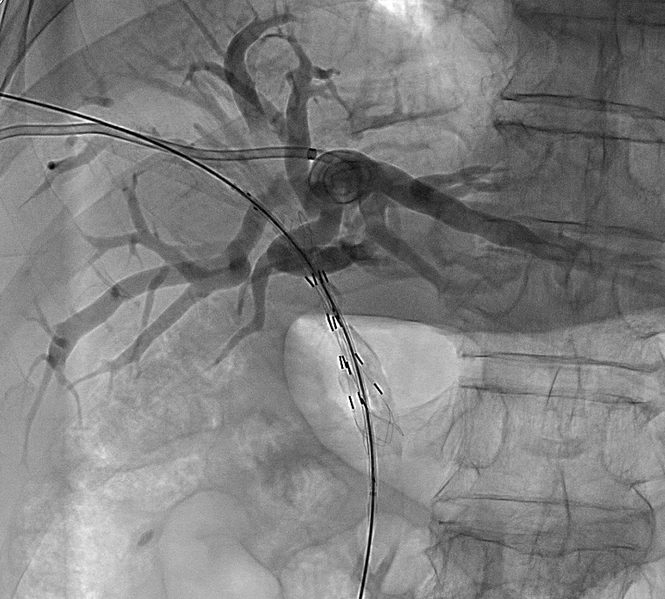

胆道粒子支架是将金属胆道支架与放射性粒子(通常为碘-125,¹²⁵I)相结合的一种创新型介入治疗手段。

将“减黄”(引流)和“抗肿瘤”(粒子)两种治疗合二为一。通常采用三腔结构,包括一个较大的胆汁引流腔和一到两个较小的粒子腔。

将携带粒子的引流管引入狭窄支架内

粒子能量在支架内局部释放,引流的同时,使支架再通